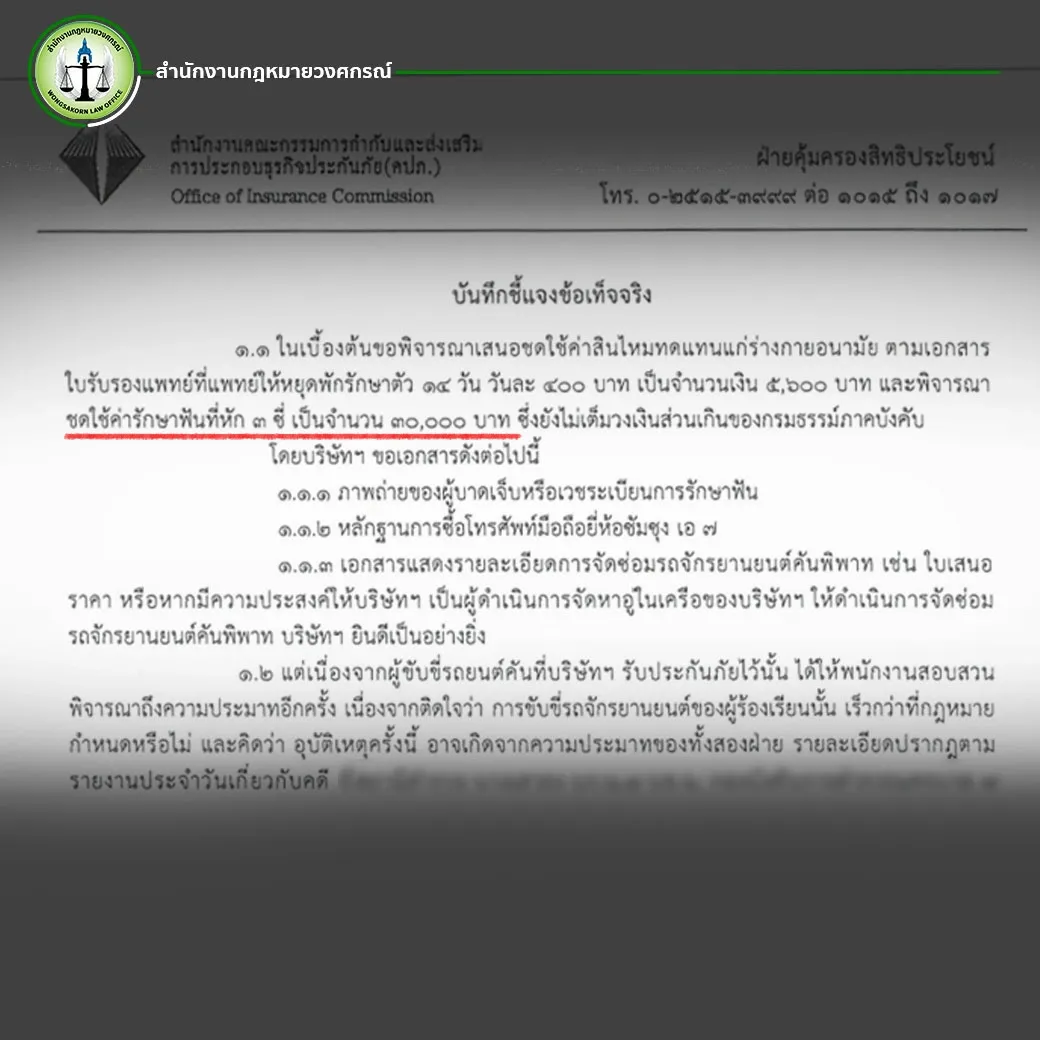

ในสถานการณ์ที่เลวร้ายแบบนี้ แต่ความเจ็บปวดและความทุกข์ทรมานของนาย A กลับไม่ได้รับการเยียวยาอย่างที่ควรจะเป็น เมื่อบริษัทประกันภัยหัวแพทย์พิจารณาชดใช้ค่ารักษาฟันที่ต้องสูญเสียรากฟันไปให้เพียง 30,000 บาทเท่านั้น ซึ่งเป็นจำนวนเงินที่ห่างไกลจากค่ารักษาจริงที่ทันตแพทย์ประเมินไว้เป็นอย่างมาก เนื่องจากนาย A ได้รับการประเมินค่ารักษาพยาบาลจากทันตแพทย์อย่างละเอียด โดยทันตแพทย์ระบุว่าความเสียหายของฟันแต่ละซี่นั้นมีมูลค่าการรักษาสูงถึง 85,000 บาทต่อซี่ สาเหตุเพราะรากฟันได้รับความเสียหายอย่างมาก ซึ่งสามารถเห็นได้ชัดเจนจากฟิล์มเอกซเรย์

นอกจากจะพิจารณาจ่ายค่ารักษาที่ต่ำกว่าความเป็นจริงอย่างมากแล้ว บริษัทประกันภัยยังขอเอกสารเพิ่มเติมจากนาย A เพื่อยื้อเวลาในการพิจารณาเพิ่มอีก นับเป็นการสร้างความเครียดและความทุกข์ใจให้กับผู้เคราะห์ร้ายอย่างมาก การขอเอกสารเพิ่มเติมและการยืดเวลาพิจารณาเช่นนี้ ดูเหมือนจะเป็นกลยุทธ์ที่บริษัทประกันภัยใช้ในทุกกรณี เพื่อหลีกเลี่ยงการจ่ายค่าสินไหมทดแทนตามที่ควรจะเป็น